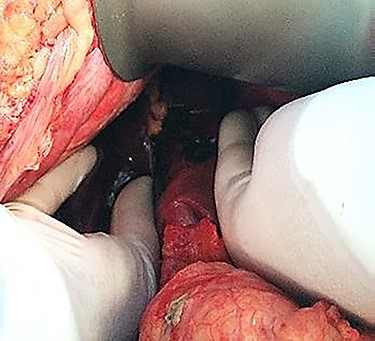

An emergency c-section was performed, during which a massive hemoperitoneum was observed. It was subsequently converted to median laparotomy and a subcapsular hepatic hematoma involving the entire left lobe was found, with rupture and active hemorrhage. Hepatic packing was performed. However, the patient continued to bleed profusely. Therefore, a Vicryl® prosthesis involving the left lobe was placed to effectively control the hemorrhage (Fig. 1).

Thirty-one-year-old pregnant woman, primigravida, with history of obesity, admitted at 35 weeks of gestation due to pain in the right abdomen with 2 weeks of evolution. On admission: hemodynamically stable with tenderness on the right quadrants of the abdomen. The initial blood work only revealed thrombocytopenia (120 × 103/μl) and impaired hepatic function (AST 65 U/L, ALT 88 U/L). The patient was kept on observation, with aggravation of symptoms. Blood work showed anemia (6.9 g/dl), thrombocytopenia (113 × 103/μl) and impaired hepatic function (AST 363 U/L, ALT 399 U/L, LDH 505 U/L). The patient underwent an emergency c-section, during which an extensive hemoperitoneum was observed. It was then converted to median laparotomy in which was observed hepatic rupture of segments V, VI and VII; packing was performed and the abdomen closed. A second-look laparotomy was performed 48 hours later. Two new subcapsular hematomas were found in the left lobe, but without active hemorrhage, which led to the removal of the packing (Figs 3–5).

As far as the surgical approach is concerned, an immediate hepatic packing was performed in both patients. However, it was not possible to fully control the hemorrhage in the first patient, so a Vicryl® prosthesis was placed, commonly used in post-traumatic splenic lacerations. It was adapted ‘in situ’ to this particular situation to cover the entire left lobe of the liver. This is an uncommon approach according to the literature. It is mainly described in the context of trauma surgery as a life-saving measure.